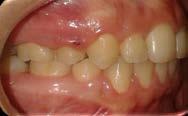

Paciente femenina de 15 años de edad que acudió a la Clínica de Ortodoncia Instituto Profesional Odontológico Contemporáneo (IPOC) en Saltillo, Coahuila, México. El motivo de su consulta fue que “quiero brackets porque sus colmillos están encimados”. Los estudios de rutina le fueron solicitados en la historia clínica SDCP. A la inspección clínica se observó paciente mesofacial, forma facial ovalada, con lado de compresión del lado derecho y lado de distracción del lado izquierdo, perfil recto, línea media facial y dental inferior no coincidían, tercio inferior aumentado, labios medianos e incompetencia labial (Figura 1).

El examen clínico intraoral reveló una clase I molar bilateral, caninos superiores en infraoclusión, por ende la clase canina no se puede clasificar, presencia de apiñamiento severo, rotaciones en premolares superiores e inferiores, línea media inferior desviada hacia el lado derecho 3.5 mm,

Figura 1. Paciente femenina 15 años de edad.

falta de coordinación de las arcadas, el arco inferior con forma cuadrada y el superior forma ovoide, el overjet de 2 mm y el overbite de 2 mm (Figura 2).